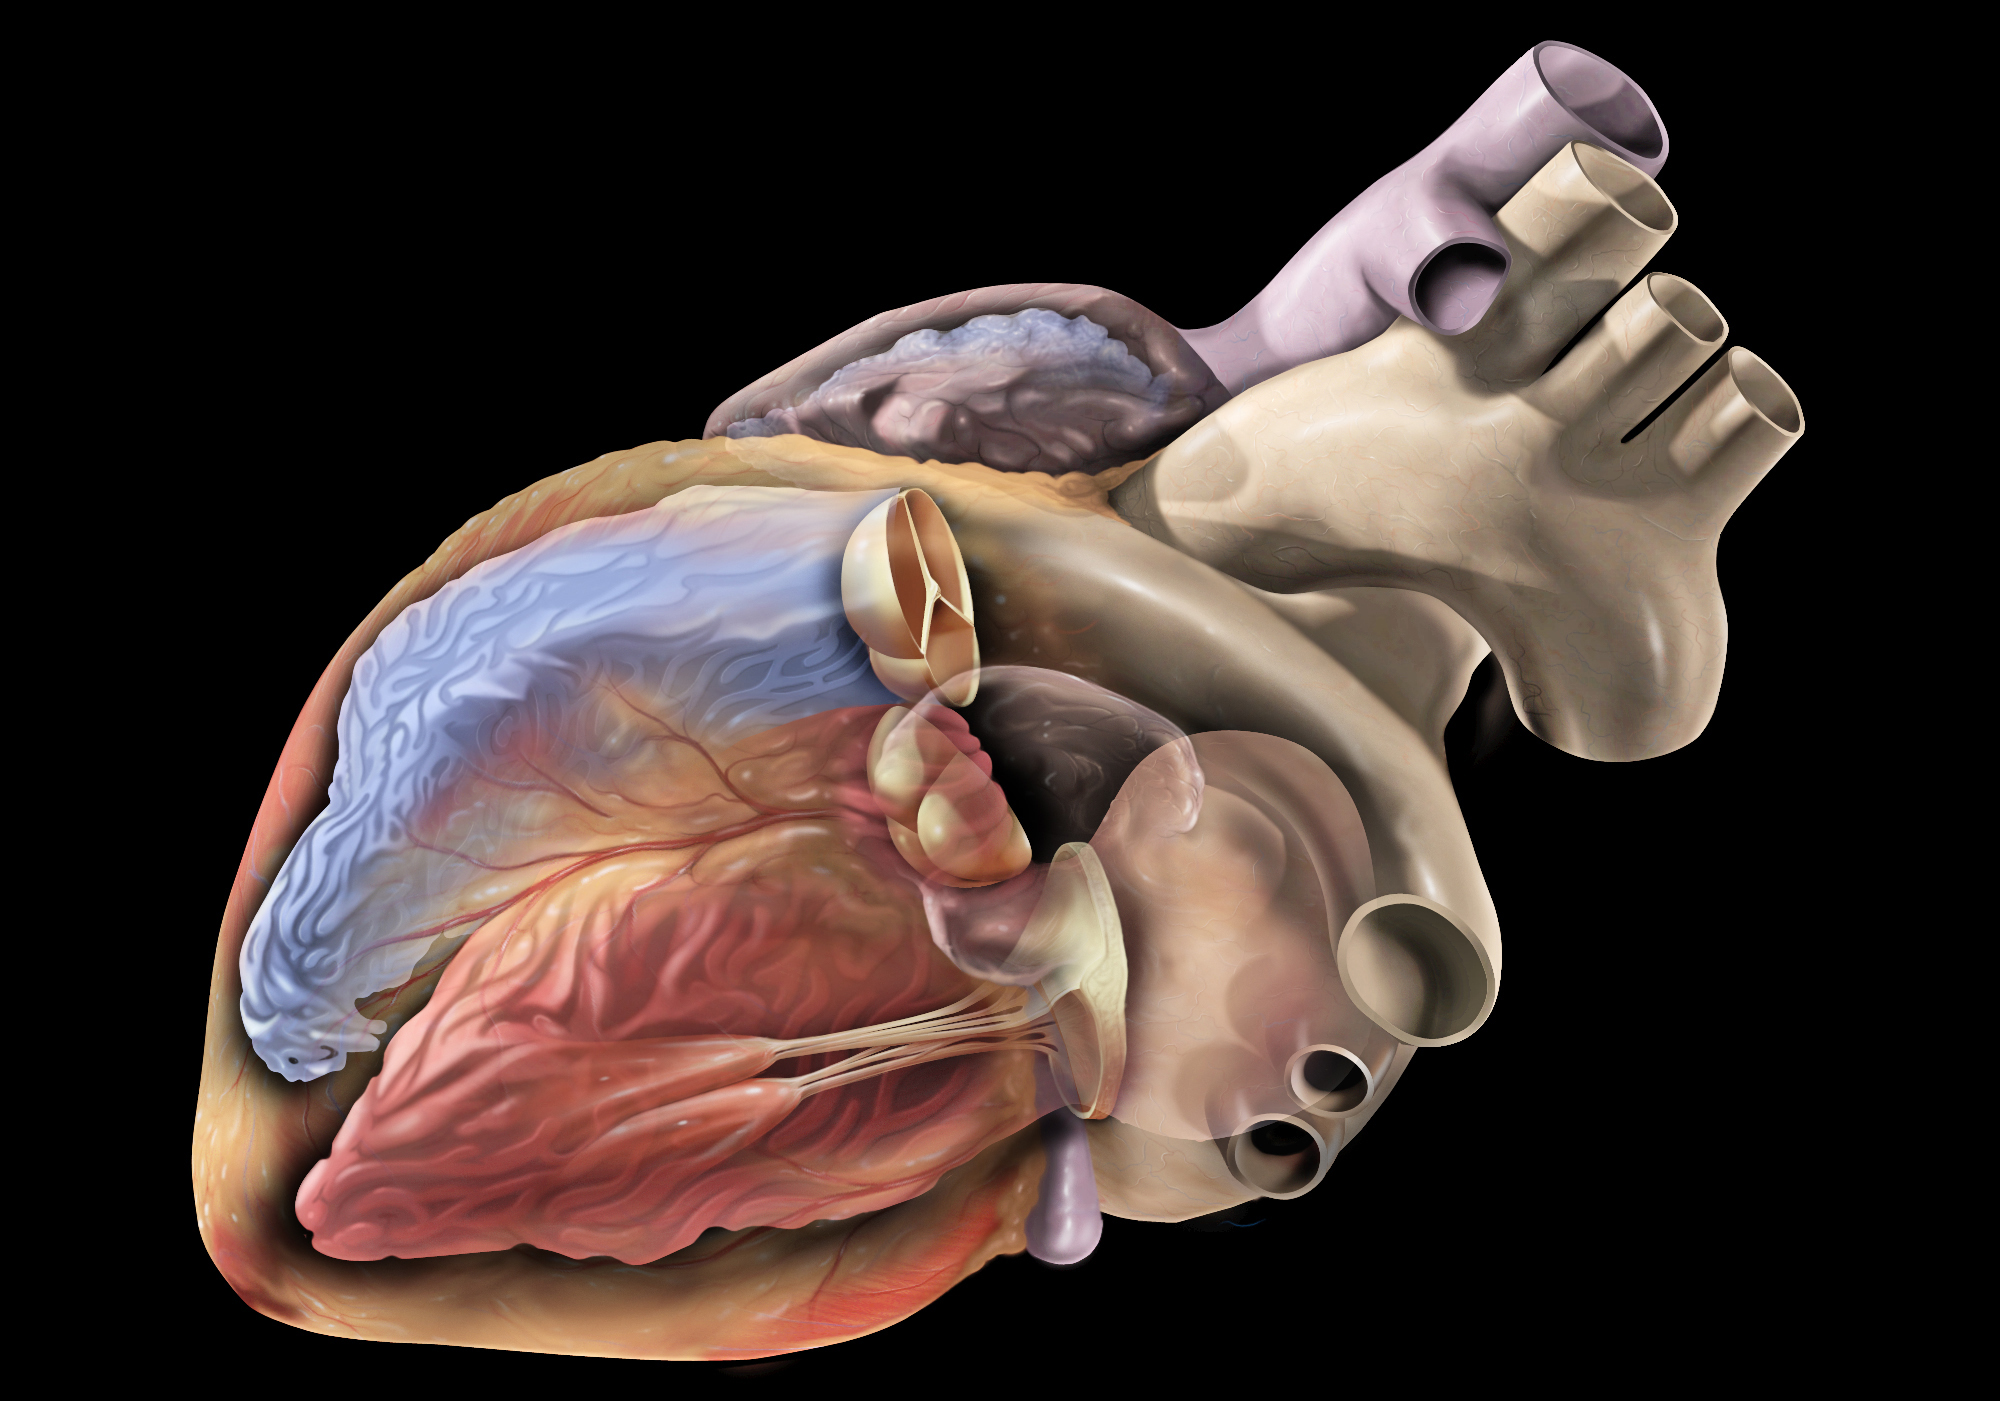

Heart disease could hit up to 28 years sooner for people, Current Diagnosis & Treatment Cardiology, Sixth Edition,